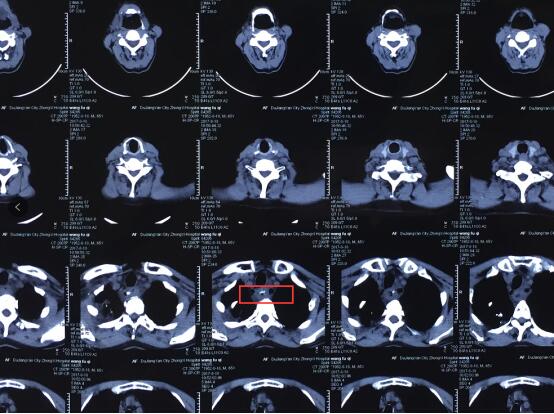

王先生的主治医生、南京仁品耳鼻喉专科医院孙高亮主任指着王先生的CT告诉笔者,卡在食道第二狭窄的鸡骨在CT上呈一白色的条状改变,清晰可见。

王先生误食的鸡骨正好牢牢横贯在食道第二个狭窄处,距离主动脉仅仅几毫米之隔,或许稍微动一动就会戳破主动脉造成致命性大出血。